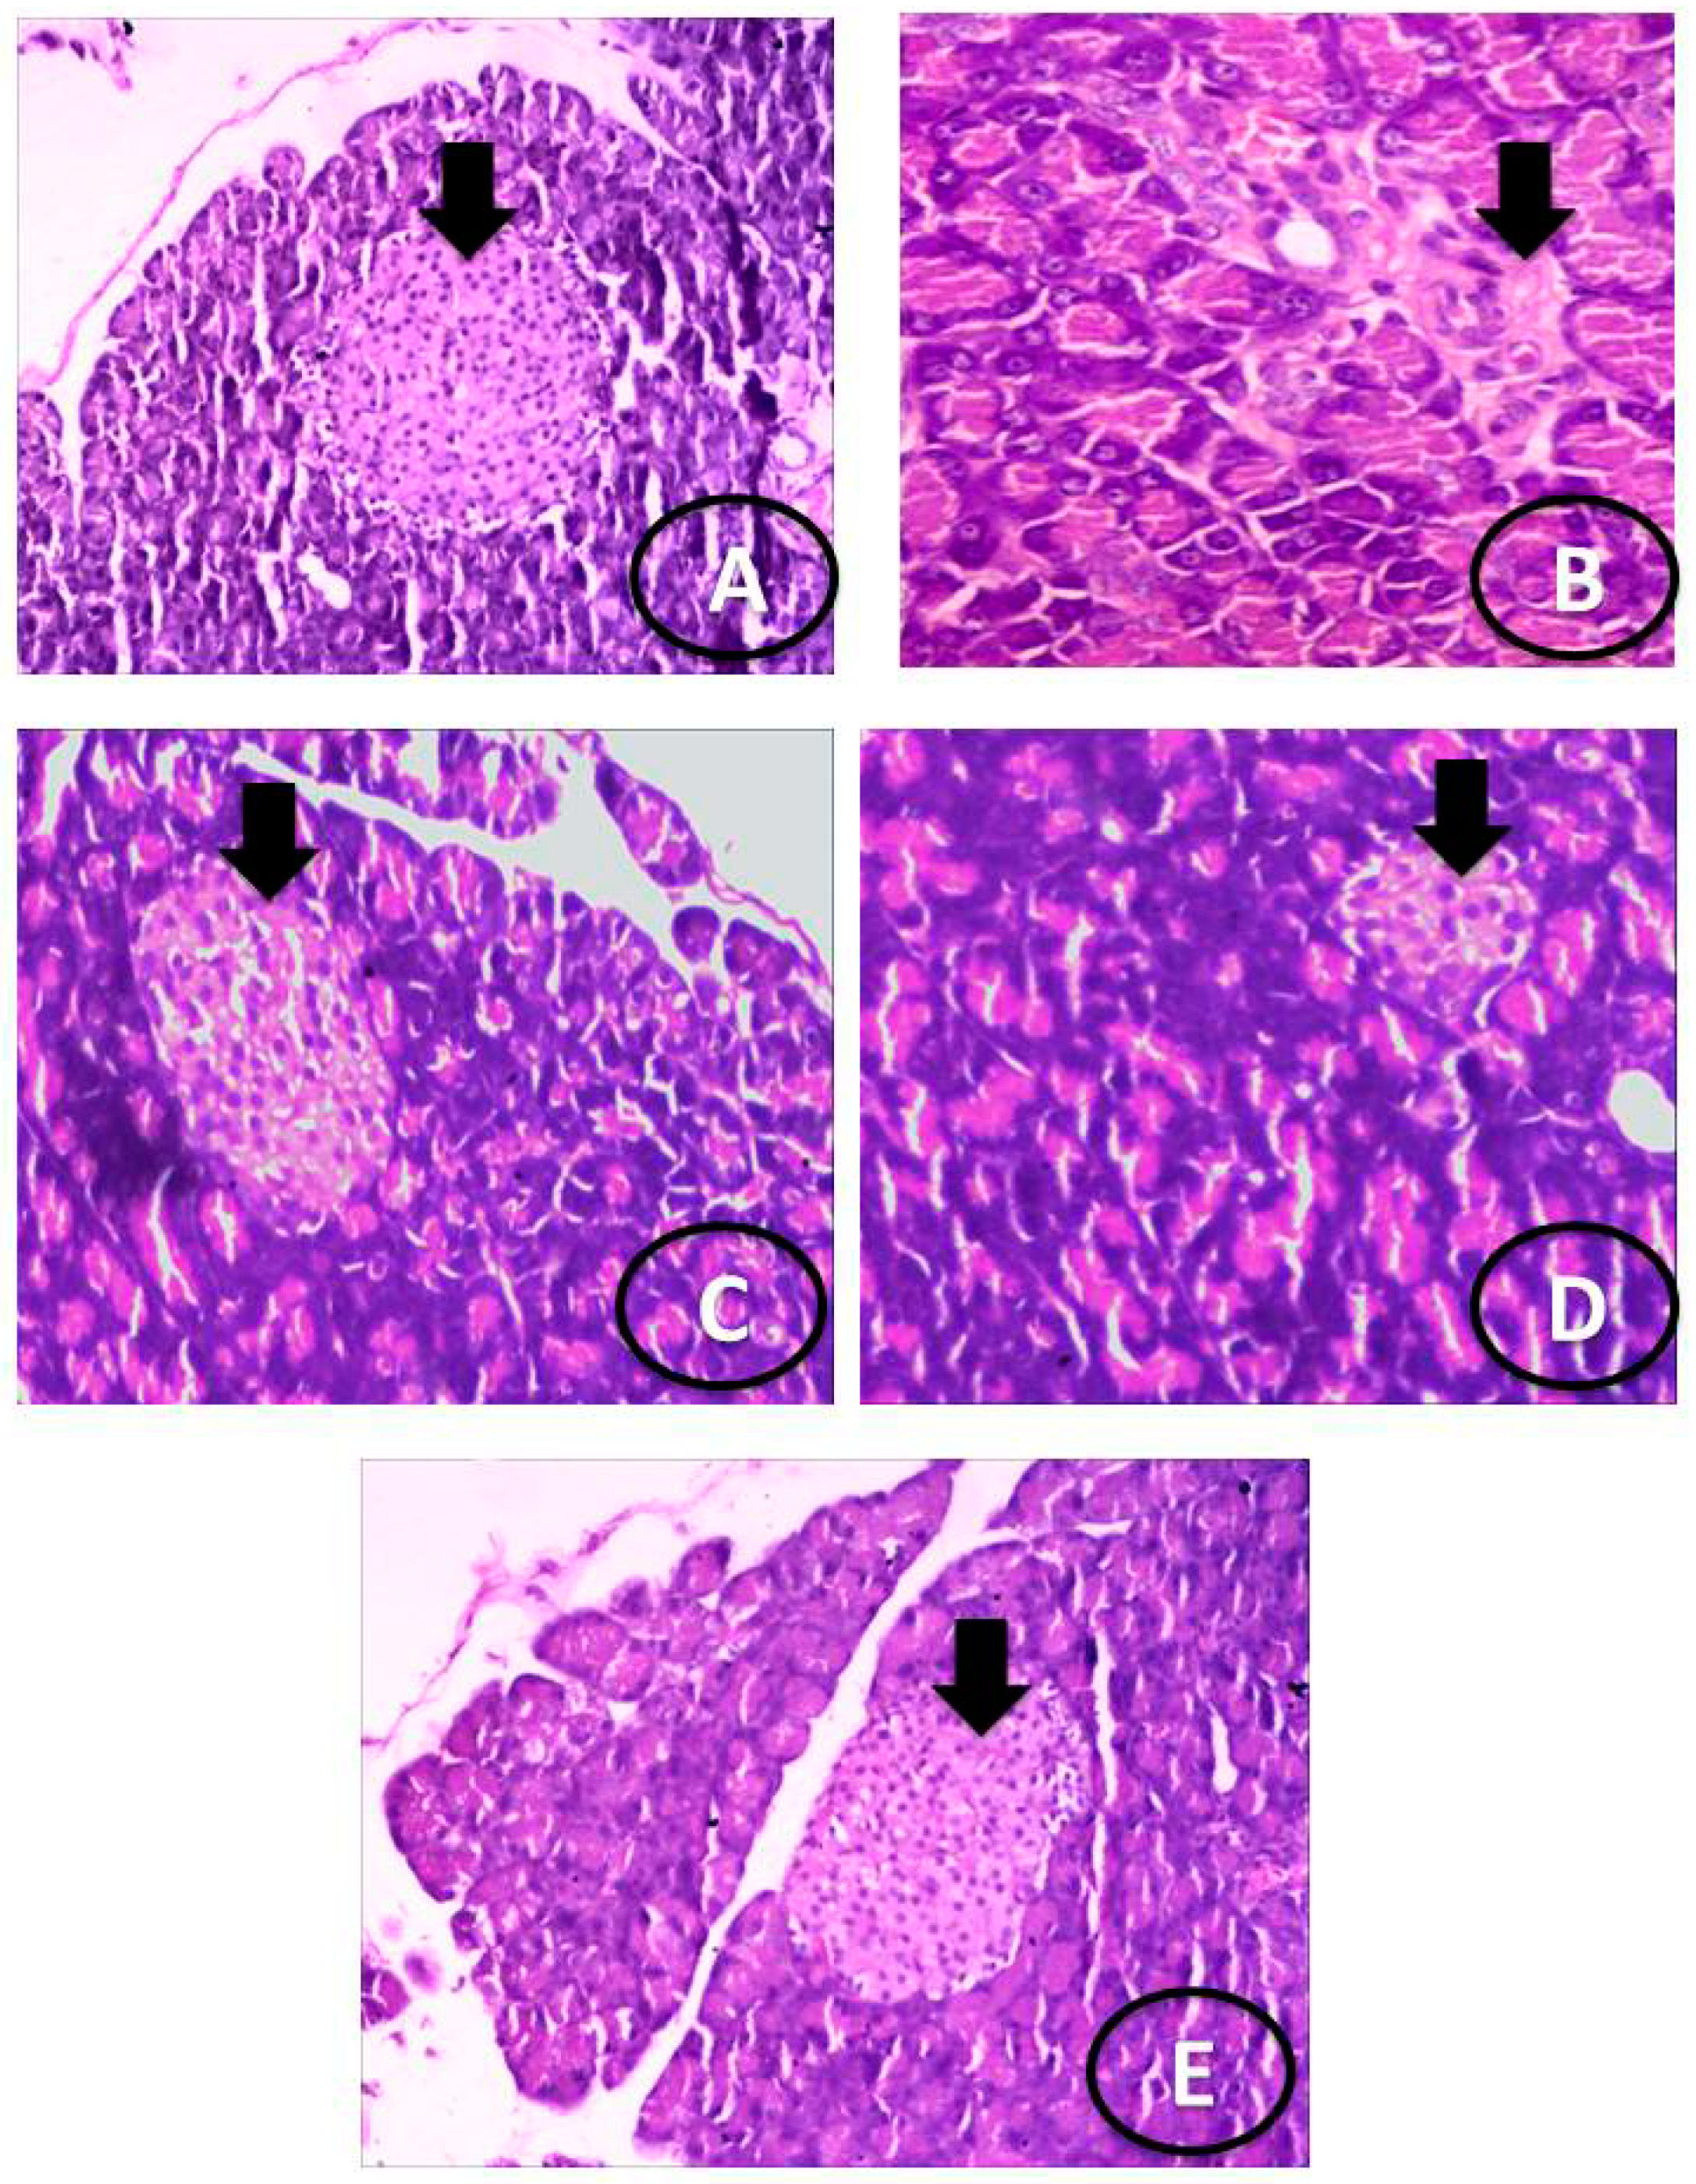

3.3. Histological Examination